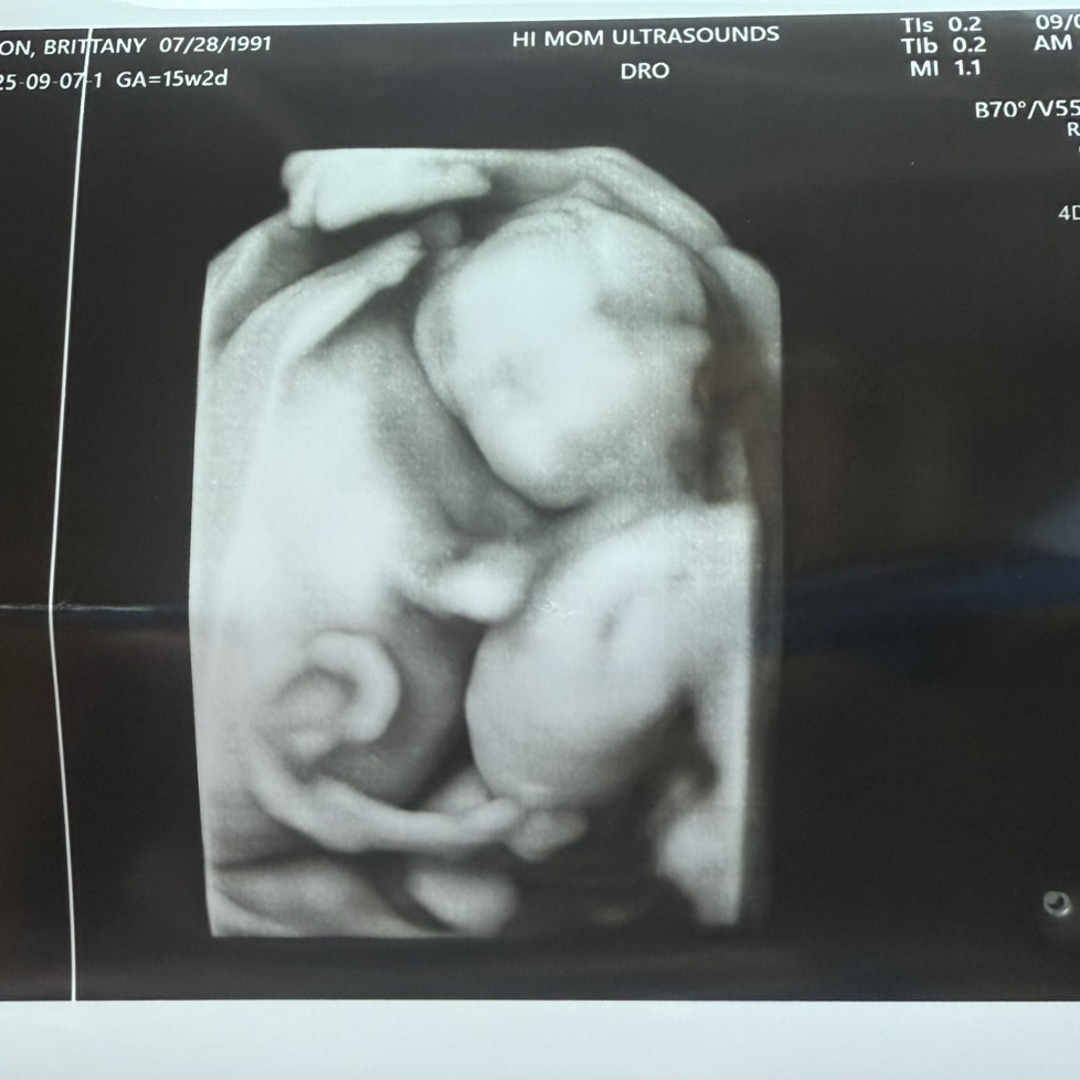

Since October 2009, we’ve celebrated every milestone together — and now our greatest one is on the way! 💙 Baby Michael Ryder Dragoon will be joining us in February 2026. Thank you for being part of our journey and for showering our little family with so much love.